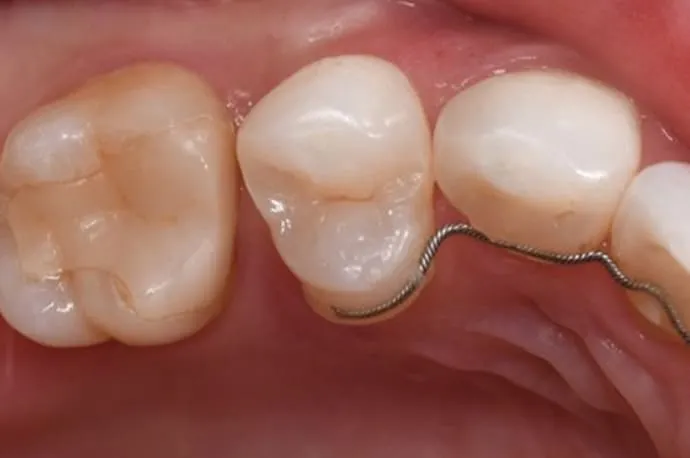

STEP 01

一見すると穴が空いていないように見えますが、内部で虫歯が広がっている状態です。